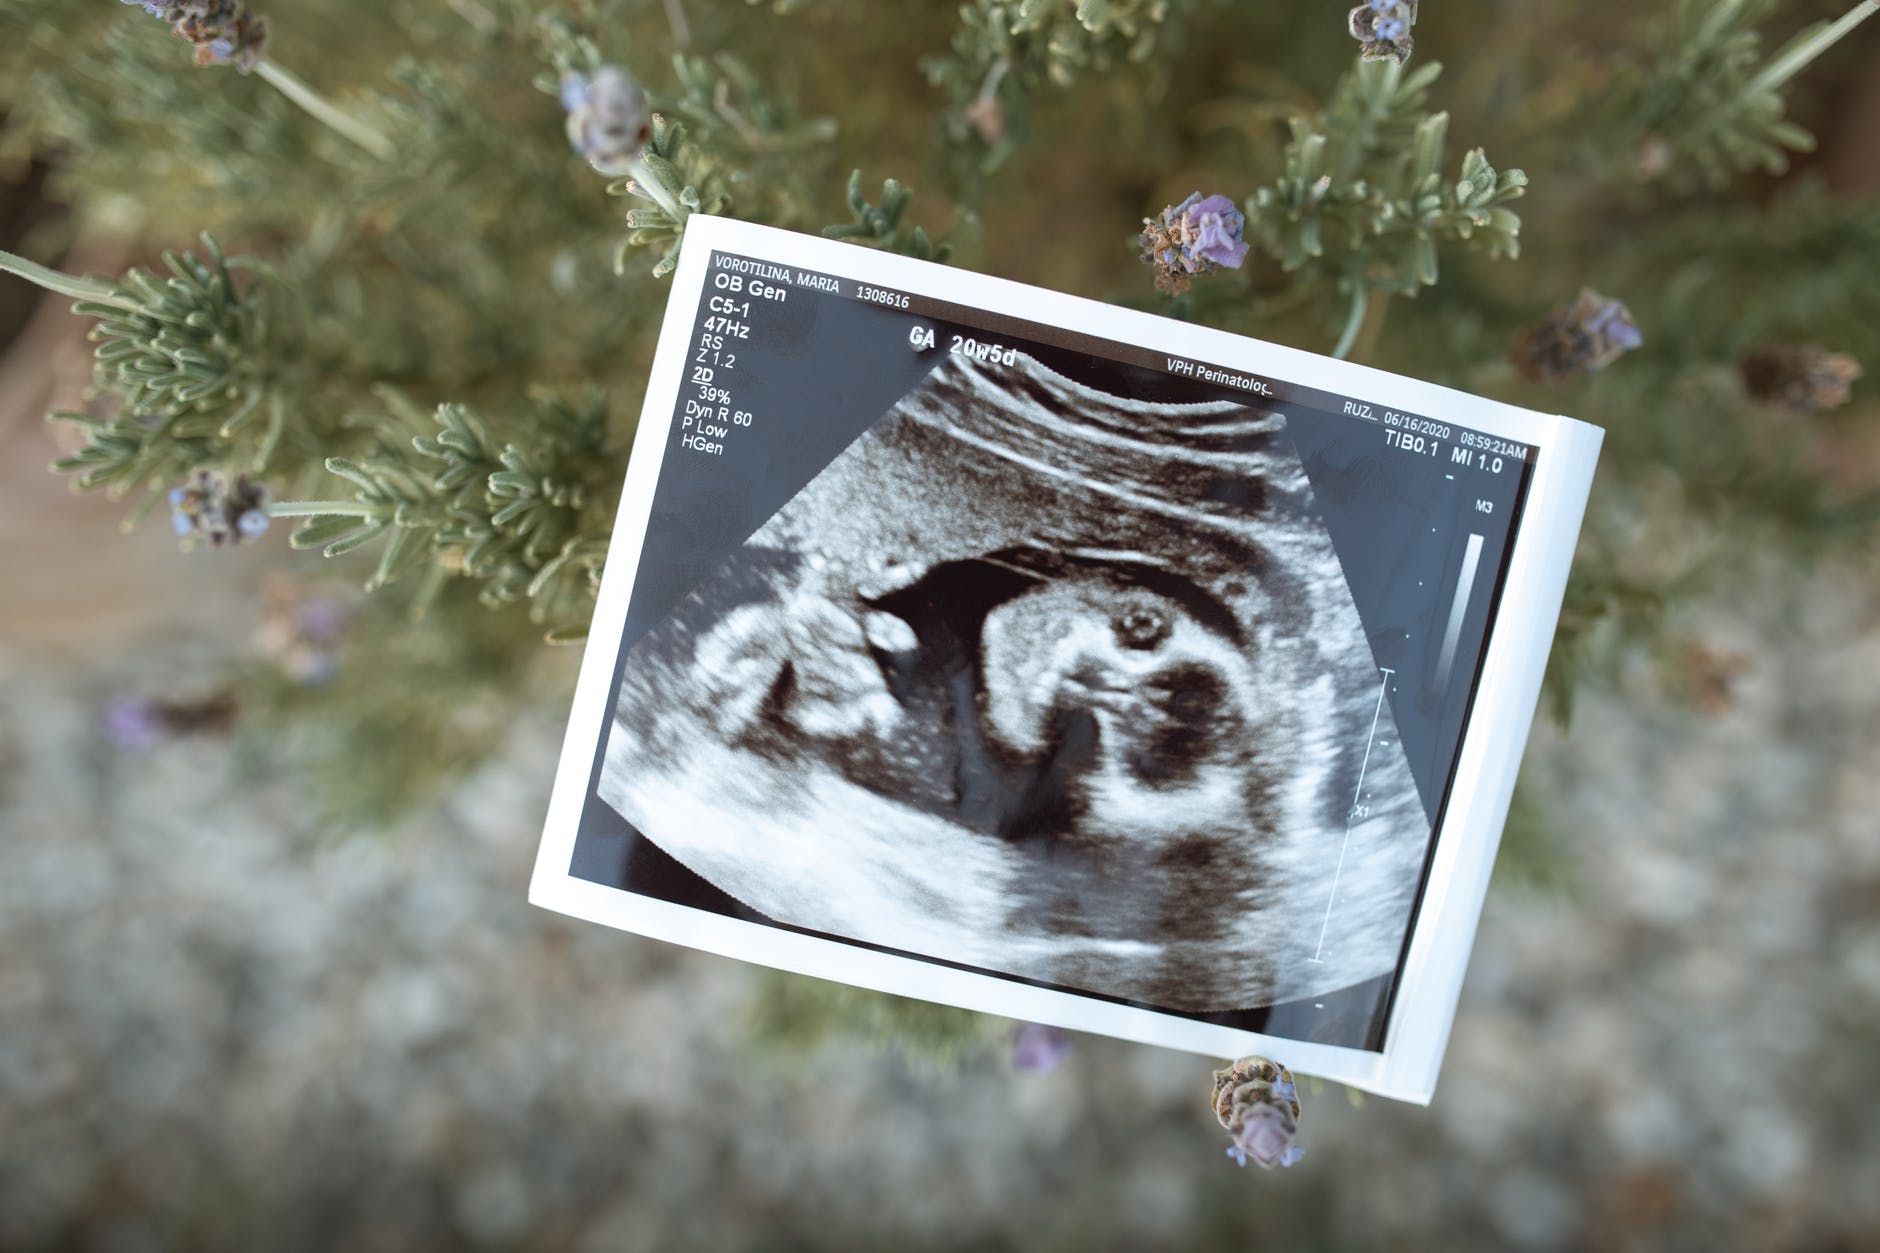

⁃ The following weeks 6-8, arms and legs are sprouting with fingers and toes. Facial features appear with oval closed eyes, nubby nose and ears, and a mouth that reflects the image of parental genes. Sensory receptors have begun and will be fully formed by 20 weeks.

⁃ The final four weeks of the first trimester finalize all the vital organs with a magnificent miniature head, and microscopic toe and fingernails. This is also a known window to reveal any potential birth defects. Regardless, a life is completely visible worthy regardless of size, level of dependence, environment, or degree of dependency.

⁃ Mom now begins to feel elegant flutters, or the baby’s awkward love taps. We can also see if the infant is a thumb sucker or not. And guess what else is revealed in weeks 13-14: Ms. Hamburger or Mr. Turtle !?!